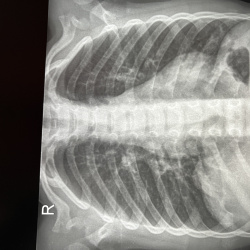

Возраст 7 лет. Жалоб нет. Что за тяжистая тень в прикорневой зоне правого лёгкого? В боковой проекции ее нет . Сначала думал может скиалогический эффект и повторил снимок, но эта же тень сохраняется...